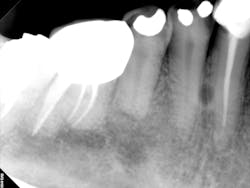

A complete mouth series was made with an incidental, well-defined, circular, radiolucent area noted between the roots of the mandibular right canine and first premolar.

For lateral periodontal cysts, there is a male predilection with a mean age of 50 years. They are typically asymptomatic and incidental findings. They are most commonly found between the lateral incisor and second premolar (mandible) and lateral incisor region (maxilla). The cyst appears as a well-defined, round/ovoid radiolucent entity. It may obliterate the lamina dura of adjacent teeth. As it enlarges, it may cause displacement and/or resorption of adjacent teeth. It is frequently single, but may be multiple. The size is typically less than 1 cm in diameter.

Differential interpretation includes keratocystic odontogenic tumor and lateral rarefying osteitis. Lateral rarefying osteitis will be associated with a nonvital tooth. The only way to determine the difference between a lateral periodontal cyst and a keratocystic odontogenic tumor is with histopathological diagnosis. Treatment is surgical excision.